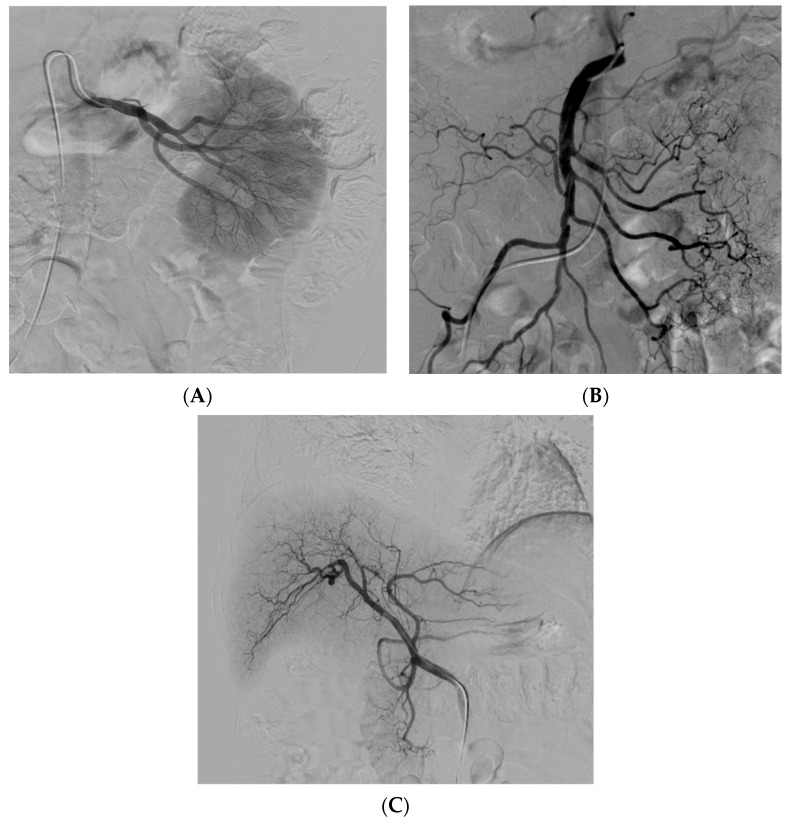

經動脈干細胞注射(TASI)可能被認為是一種理想的選擇性遞送方法,在所需器官中具有最佳分布和高干細胞濃度。在組織取樣和干細胞分離處理(自體或異體)之后,該過程基本上包括通過動脈通路(最常見的是股動脈)引入導管。然后,在熒光鏡和造影劑引導下,將導管放置在所需的供血動脈(肝動脈、腸系膜動脈或腎動脈)中,以進行隨后的干細胞注射。圖2)。

導管定位確保對所需組織進行選擇性治療,避免非目標干細胞輸注。